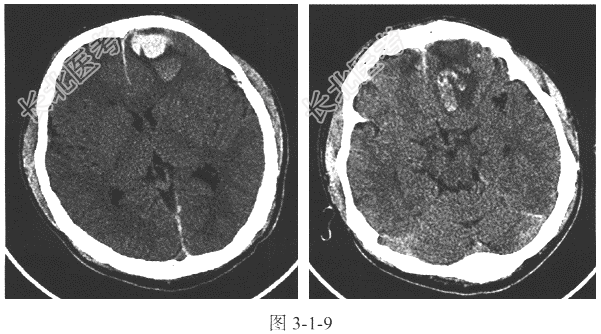

- [材料题] 患者,男,28岁,不慎摔伤头部1天,急诊CT示左侧前额叶见团块状高密度影,周围见片状水肿带,边界清,右侧额叶见斑片状低密度影(图3-1-9)。

- 简答题1、患者CT检查的主要影像表现是什么?

- 简答题2、综合上述病史,应考虑何种疾病?如何确诊?